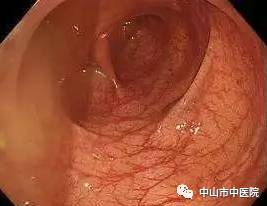

医生说,这样的肠粘膜改变,称之为“大肠黑变病”,在日常检查过程中检出率不低,但是像这位患者这样黑的,实属罕见。而正常的肠子,是粉红粉红、血管纹理分明的,如下图: